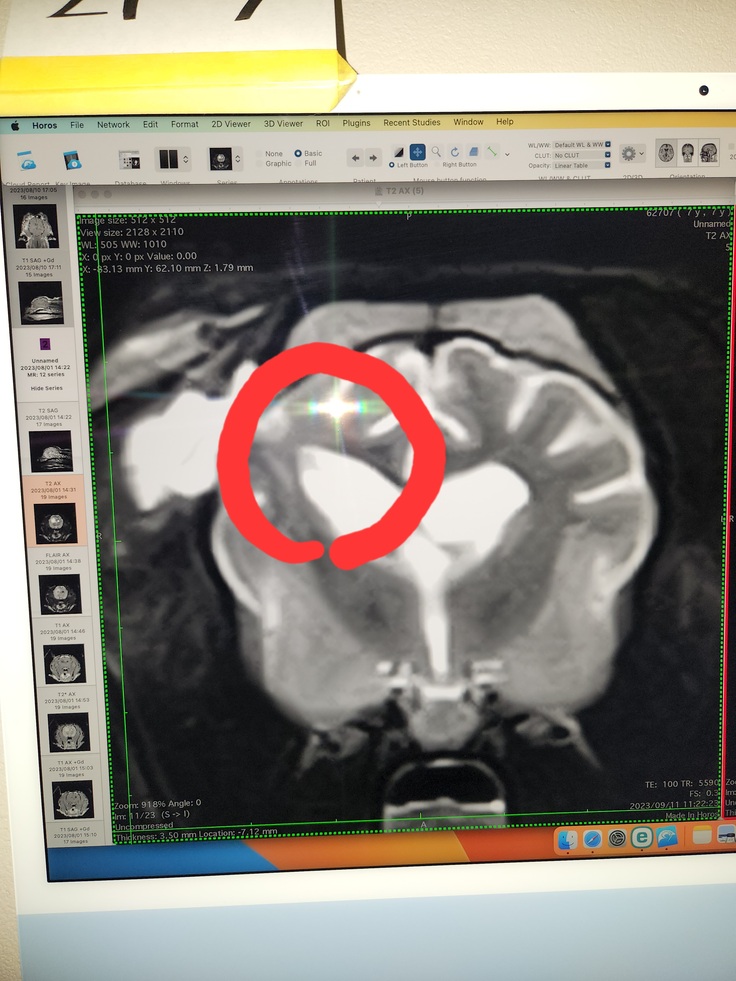

脳腫瘍摘出手術をして病理組織診断で希突起嘐細胞腫(びまん性グリオーマgrade3)と分かりました。

2023年8月1日に検査を受けに行きました。麻酔のリスクも心配でしたが無事に検査を終えて画像をみると2cmの腫瘍が見つかりました。

先生が検査結果でてんかん発作はおそらくこの腫瘍が原因で、このままでは脳が圧迫され歩けなくなったり、呼吸も止まりますと言われ緊急を要する手術でした。

9月11日に放射線治療を受ける為の準備があり再びMRIなど受けました。

桜子の今の脳の状態の説明があり、残念

ことに取り切れなかった腫瘍がありました。